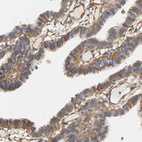

Immunohistochemical staining of human fallopian tube shows strong cytoplasmic granular positivity in glandular cells.